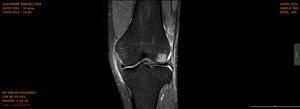

Estou cursando Bacharel em Educação Física e na aula prática de Handebol, num lance atacando da ponta esquerda pro meio, saltei para arremessar e ao aterrissar com a perna esquerda o marcador bateu do lado do meu joelho (com certeza sem querer) e ele “dobrou” no sentido que não era pra “dobrar” (sentido valgo), na hora eu senti um estalo interno, veio a dor e caí no chão.

Com o valor arrecadado irei pagar todo o custo da cirurgia de reconstituição do LCA (Ligamento Cruzado Anterior) e LCM (Ligamento Colateral Medial), incluindo hospital, equipe médica e materiais.